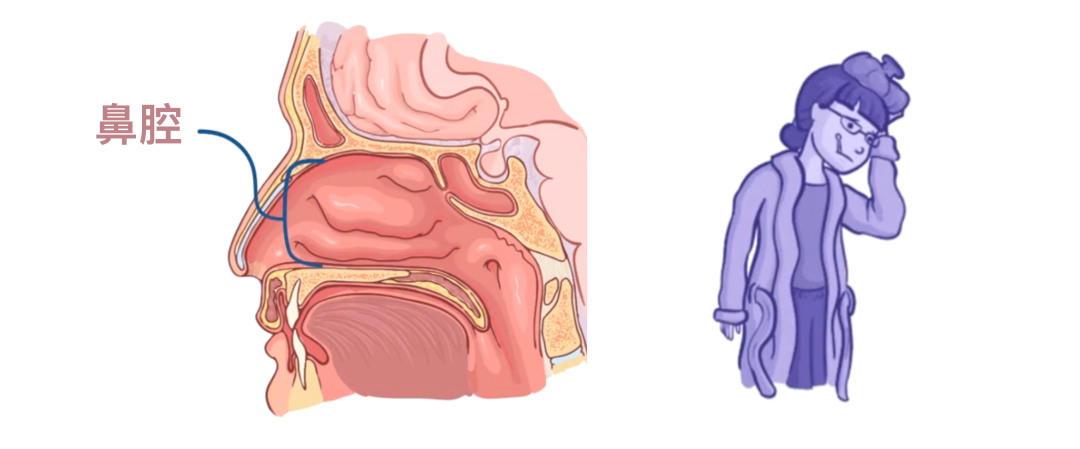

有趣的是,肺炎链球菌实际上可以在鼻腔和鼻窦中“和平”定植,只要免疫系统能够控制它们,限制其生长并阻止它们扩散到身体其他部位,就不会造成危害。

例如鼻窦炎,即鼻腔和副鼻窦的黏膜发生炎症,表现为发热、面部疼痛和头痛。

有时,当副鼻窦壁非常薄时,肺炎链球菌可能会进入颅腔,从而导致脑膜炎。